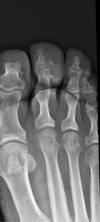

4

5